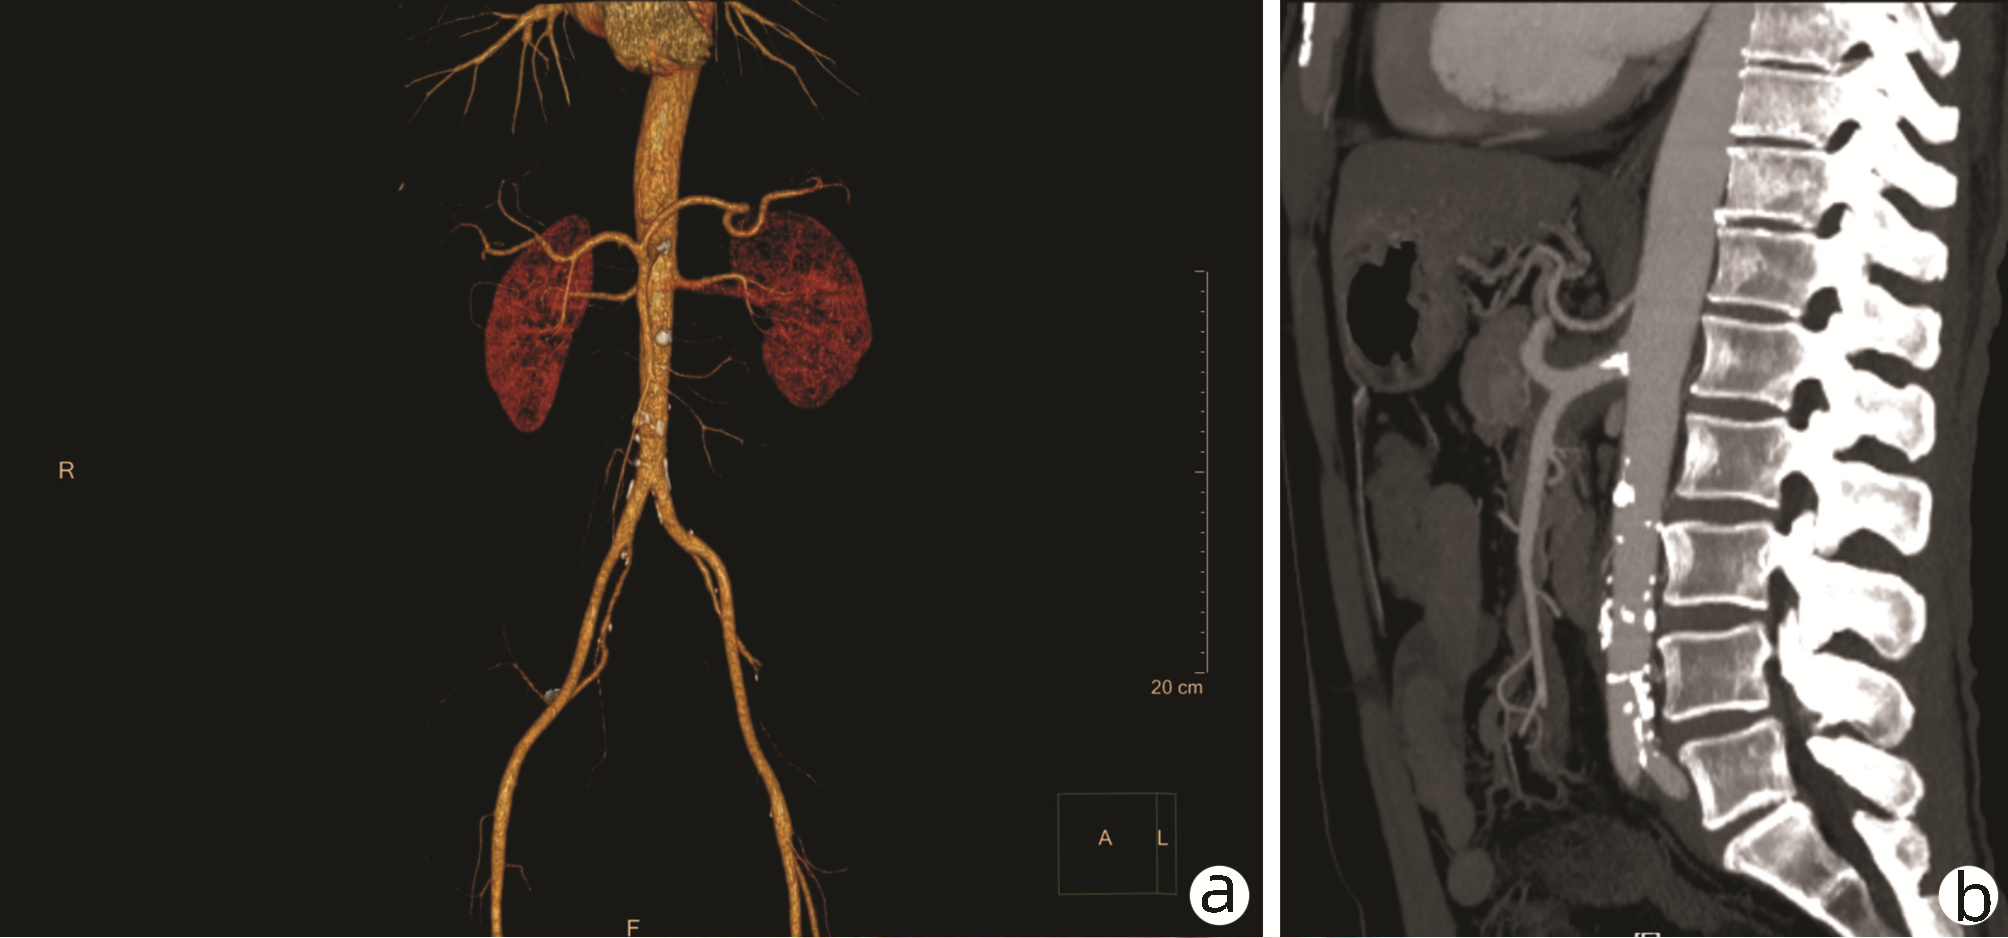

IgG4-related retroperitoneal fibrosis: A case report

Zhaoxia LI, Yang LIU, Nan LI, Zhuhui JI, Guijie XIN

2022, 38(5): 1126-1128. DOI: 10.3969/j.issn.1001-5256.2022.05.030

Abstract(758) HTML (364) PDF (2161KB)(55)

Abstract: